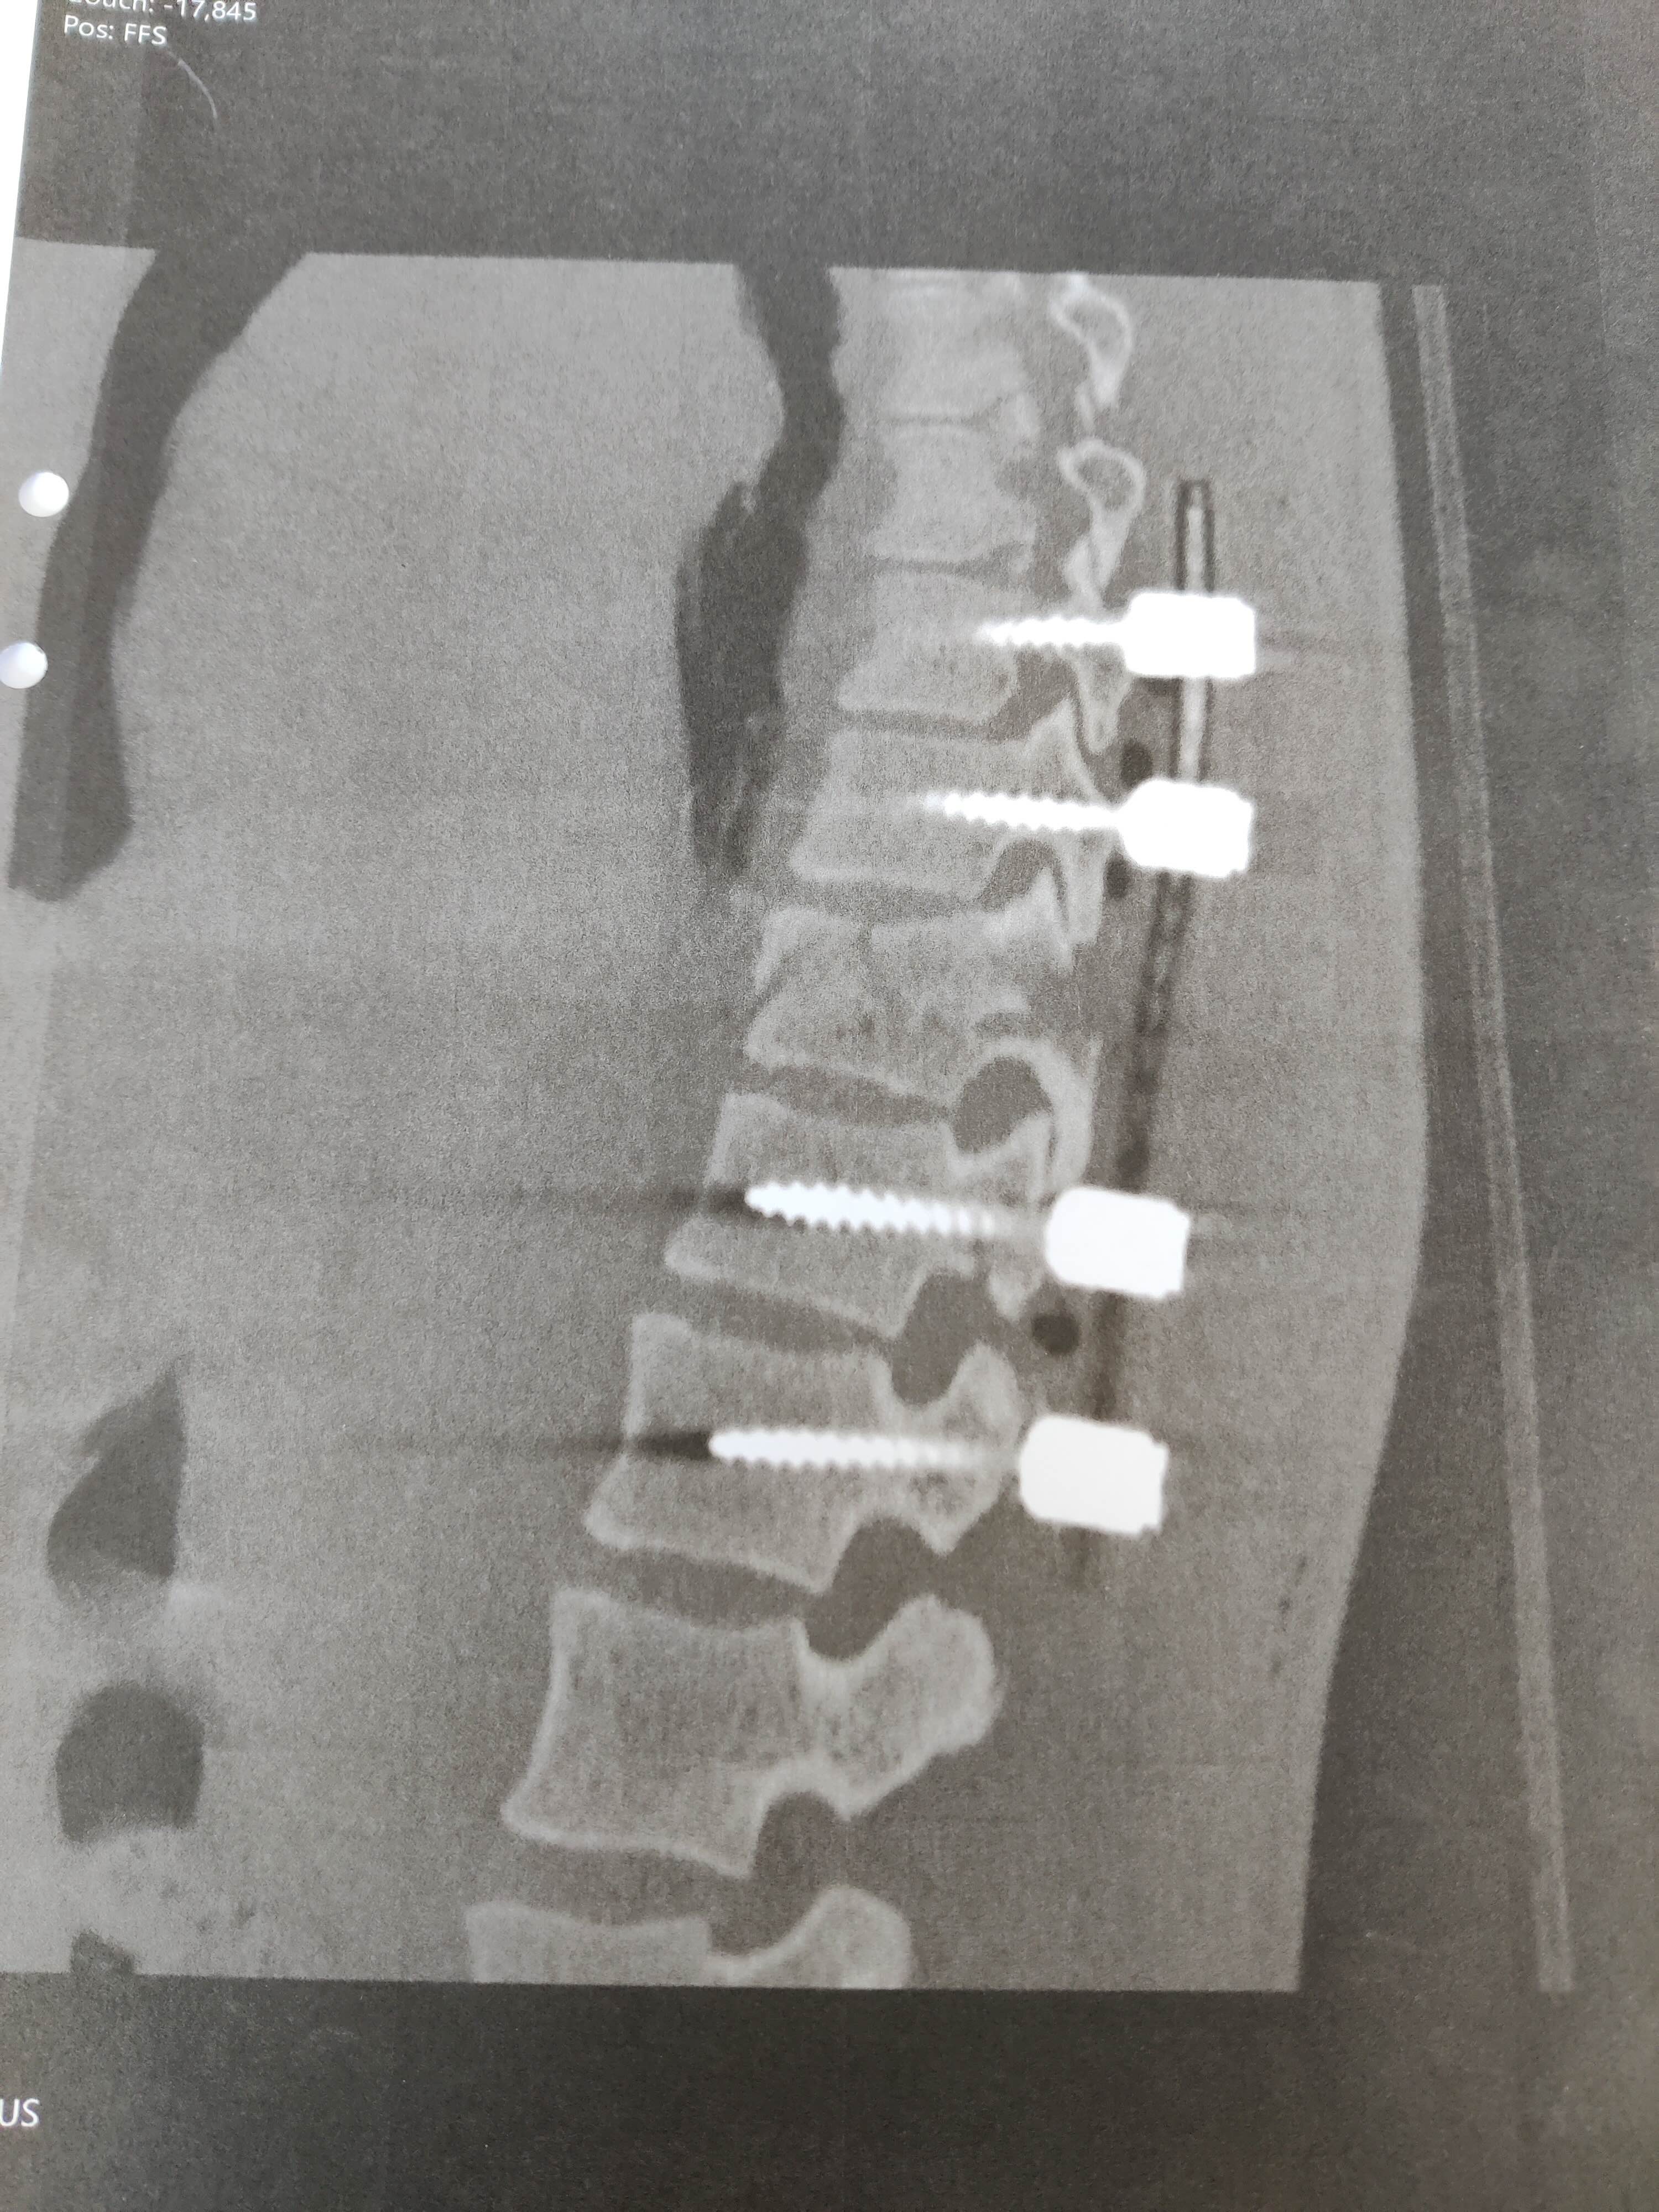

Röntgen visade en instabil fraktur på en kota i bröstryggen, en spricka i nackkotan, sex brutna revben och sju deciliter blod i höger lunga. Till råga på allt hade hon även brutit vänster handled. Frakturen på kotan i bröstryggen skulle opereras. Natten kom och Karolina Svensson Magnusson fick åka ambulansflyg till Norrlands universitetssjukhus i Umeå och efter en magnetkameraundersökning dagen efter var det dags för operation. Operationen slutade med åtta skruvar och två stag för att stabilisera ryggen.

– När jag vaknade upp försökte jag röra mina ben och när jag insåg att jag kunde det somnade jag om igen. Jag hade en väldig tur att ryggmärgen inte var påverkad, och kirurgen berättade sedan för mig att operationen hade gått bra och att det såg lovande ut inför framtiden.